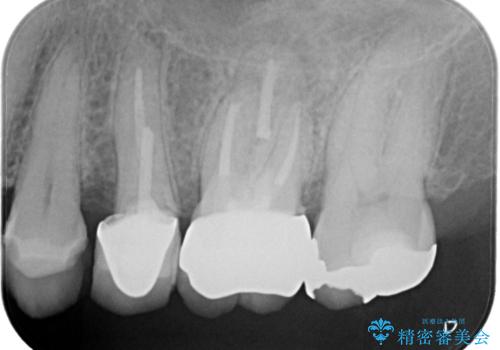

- 患者様は、左上第一小臼歯の垂直性歯根破折が確認され、抜歯が必要となりました。本来、抜歯即時埋入を適用できるケースでしたが、患者様のご都合によりブリッジとインプラントで一度悩まれるとのことで待時埋入となりました。治療計画では、上顎の骨の状態を慎重に評価し、デンサーバーを用いてドリリングを行うことで、上顎洞粘膜を傷つけずにインプラントを埋入する方法を選択しました。埋入後の安定を確保するため、術後の経過観察を慎重に行います。

待時埋入では、抜歯後に骨の再生を待つ必要があり、即時埋入に比べて治療期間が長くなります。しかし、デンサーバーを使用した精密なドリリングによって、上顎洞粘膜を破らずにインプラントを埋入することができ、術後の合併症リスクを最小限に抑えることができました。インプラント埋入後は、骨との結合を待ちながらしっかりとしたケアと定期的な検診を行い、最終的な補綴物の装着に備えます。